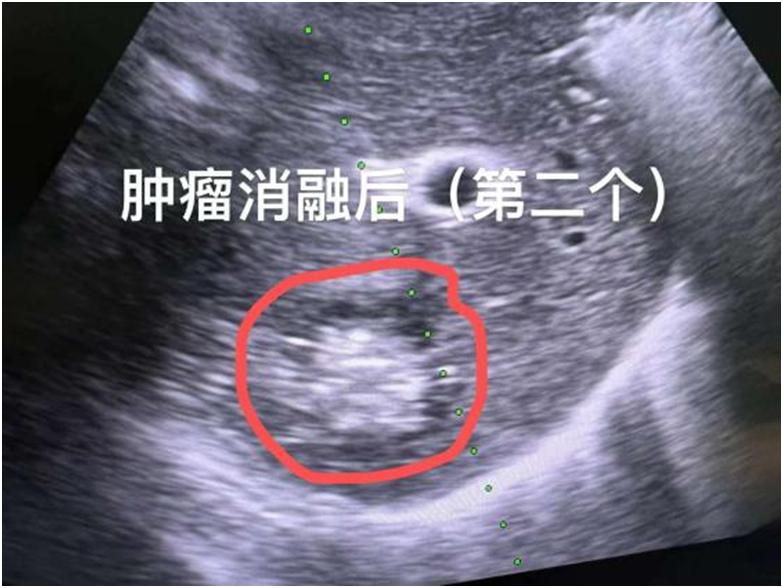

入院完善相关检查发现,患者肝右叶局部呈术后缺如,肝S2、S6段各见一低回声肿物,大小分别约35mmx34mm、50mmx36mm,边界清,内回声不均匀,CDFI示肿物边缘可见点状血流信号,考虑为转移瘤。针对患者的往期病史,专家在经过其及家属同意后,为他施行肝脏肿瘤微波消融术。术中以右前上腹壁肝脏S2、S4段肿瘤体表投影区肋间皮肤为穿刺点,以肝脏S2、S4段肿瘤为靶区,先后用微波刀经穿刺点穿刺到靶区,超声扫描到位后,分别以50W功率消融,各消融5分钟,待消融范围覆盖上述靶区,拔除微波刀,贴上敷料,完成手术。